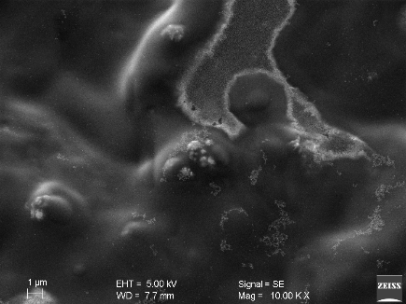

By scanning electron microscope (SEM)

Surface morphological properties of formula F2 nano size vesicles were obtained by SEM at three magnifications (1.00 K X, 5.00 K X, 10.00 K X) and shown in fig. 11. The vesicular properties of these drug carriers form double layers. SEM revealed the morphology of the vesicles and the arrangement of the lamellar structure encapsulating the drug molecules [34].

(A) (B) (C)

Fig. 11: Scanning electron micrographs of proniosomal formula F2 at three different magnification powers (A)1.00 K X, (B)5.00 K X, (C)10.00 K X)